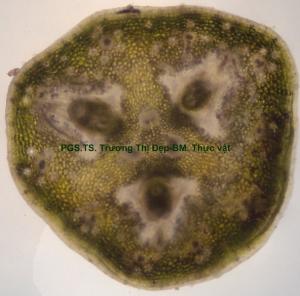

Cuống lá [hình 32]

Vi phẫu tiết diện gần tròn một đầu bằng. Lớp biểu bì hơi dợn sóng, tế bào hình chữ nhật, kích thước lớn hơn tế bào mô dày, đều, cutin mỏng. Mô dày [hình 33] góc 2-4 lớp tế bào đa giác gần tròn, kích thước không đều. Mô mềm vỏ đạo nhiều lớp tế bào đa giác, kích thước lớn hơn tế bào mô dày, không đều, xếp lộn xộn. Ống tiết ly bào nhiều trong vùng mô mềm vỏ và mô dày. Trụ bì hoá mô cứng 2-3 lớp tế bào không liên tục bên ngoài libe. Nhiều bó libe gỗ [hình 34] xếp thành vòng không liên tục, libe ở ngoài gỗ ở trong. Gỗ và libe có cấu tạo cấp 2. Libe 1 xếp thành từng cụm bên dưới trụ bì. Libe 2 nhiều lớp tế bào đa giác, kích thước không đều, xếp thành dãy xuyên tâm. Mạch gỗ 2 tế bào đa giác gần tròn, xếp rải rác trong mô mềm gỗ; mô mềm gỗ tế bào đa giác xếp thành dãy. Gỗ 1 tập trung thành từng cụm từ 3-5 bó, mỗi bó từ 2-3 mạch gỗ nằm trong mô mềm gỗ vách cellulose. Mô mềm tủy đạo tế bào hình đa giác hoặc đa giác gần tròn, kích thước không đều, 2-4 lớp tế bào dưới gỗ 1 vách tẩm chất gỗ mỏng.

[hình 35]